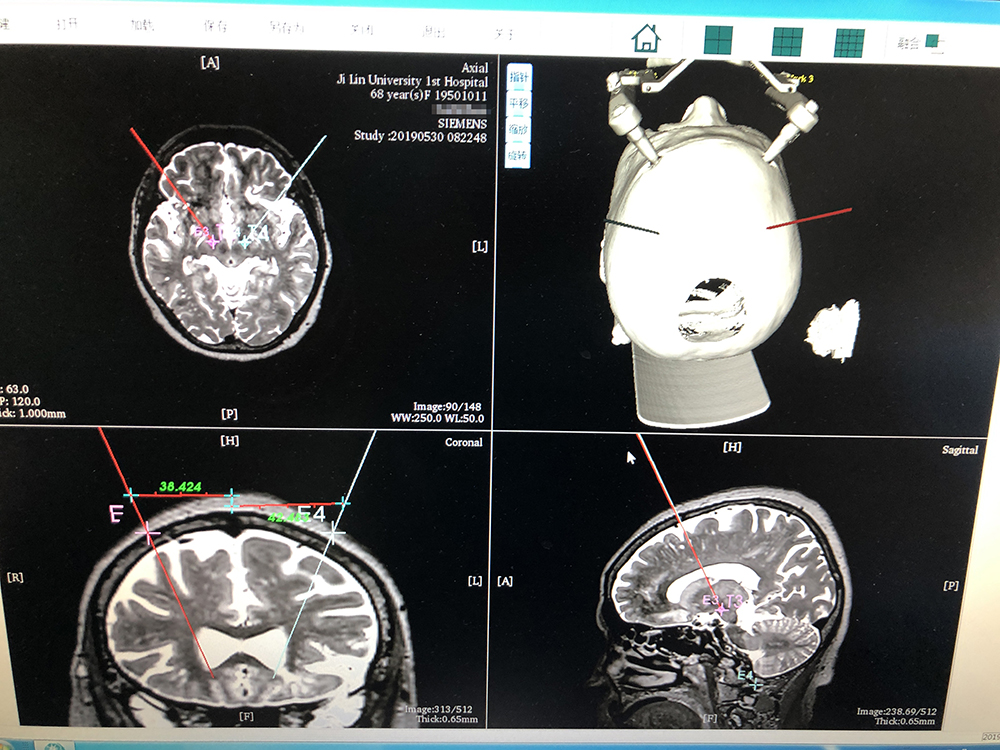

術(shù)前,邱吉慶教授借助“睿米”神經(jīng)外科手術(shù)機(jī)器人配套軟件,為患者制定雙側(cè) STN 核團(tuán)植入電極的手術(shù)路徑規(guī)劃。

alt text

借助“睿米”軟件制定手術(shù)規(guī)劃